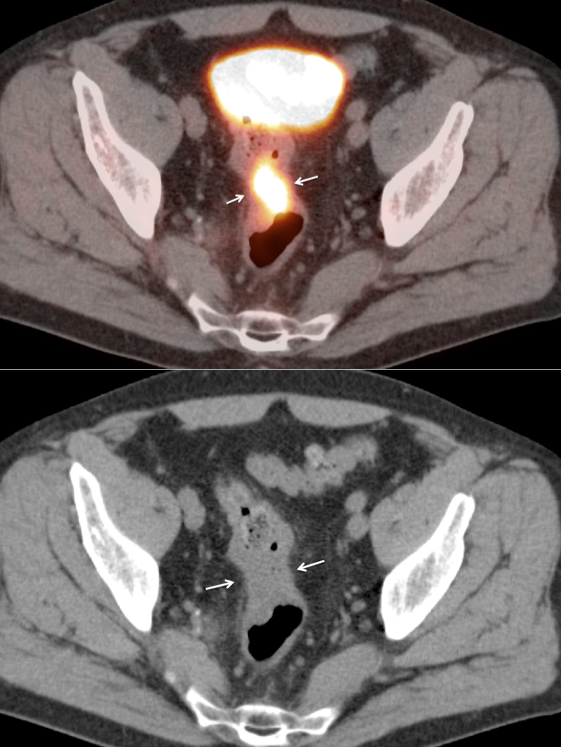

Presentation of Primary Cancer

• Focal bowel uptake, usually with associated bowel wall thickening.

• Normal physiologic bowel uptake (discussed here) can be very focal and isolated to only one part of the colon, most commonly the cecum and rectum. Always look for associated bowel wall thickening on the CT images.

• Beware the small rectal cancer!  As the ano-rectal region frequently demonstrates intense physiologic uptake, it is very easy to overlook a rectal malignancy, especially if it is an incidental finding.  To avoid this error, always evaluate the rectum carefully on the sagittal whole body images.  It is shocking to see how readily apparent a rectal cancer can be on these images, yet so easily overlooked in the axial plane.